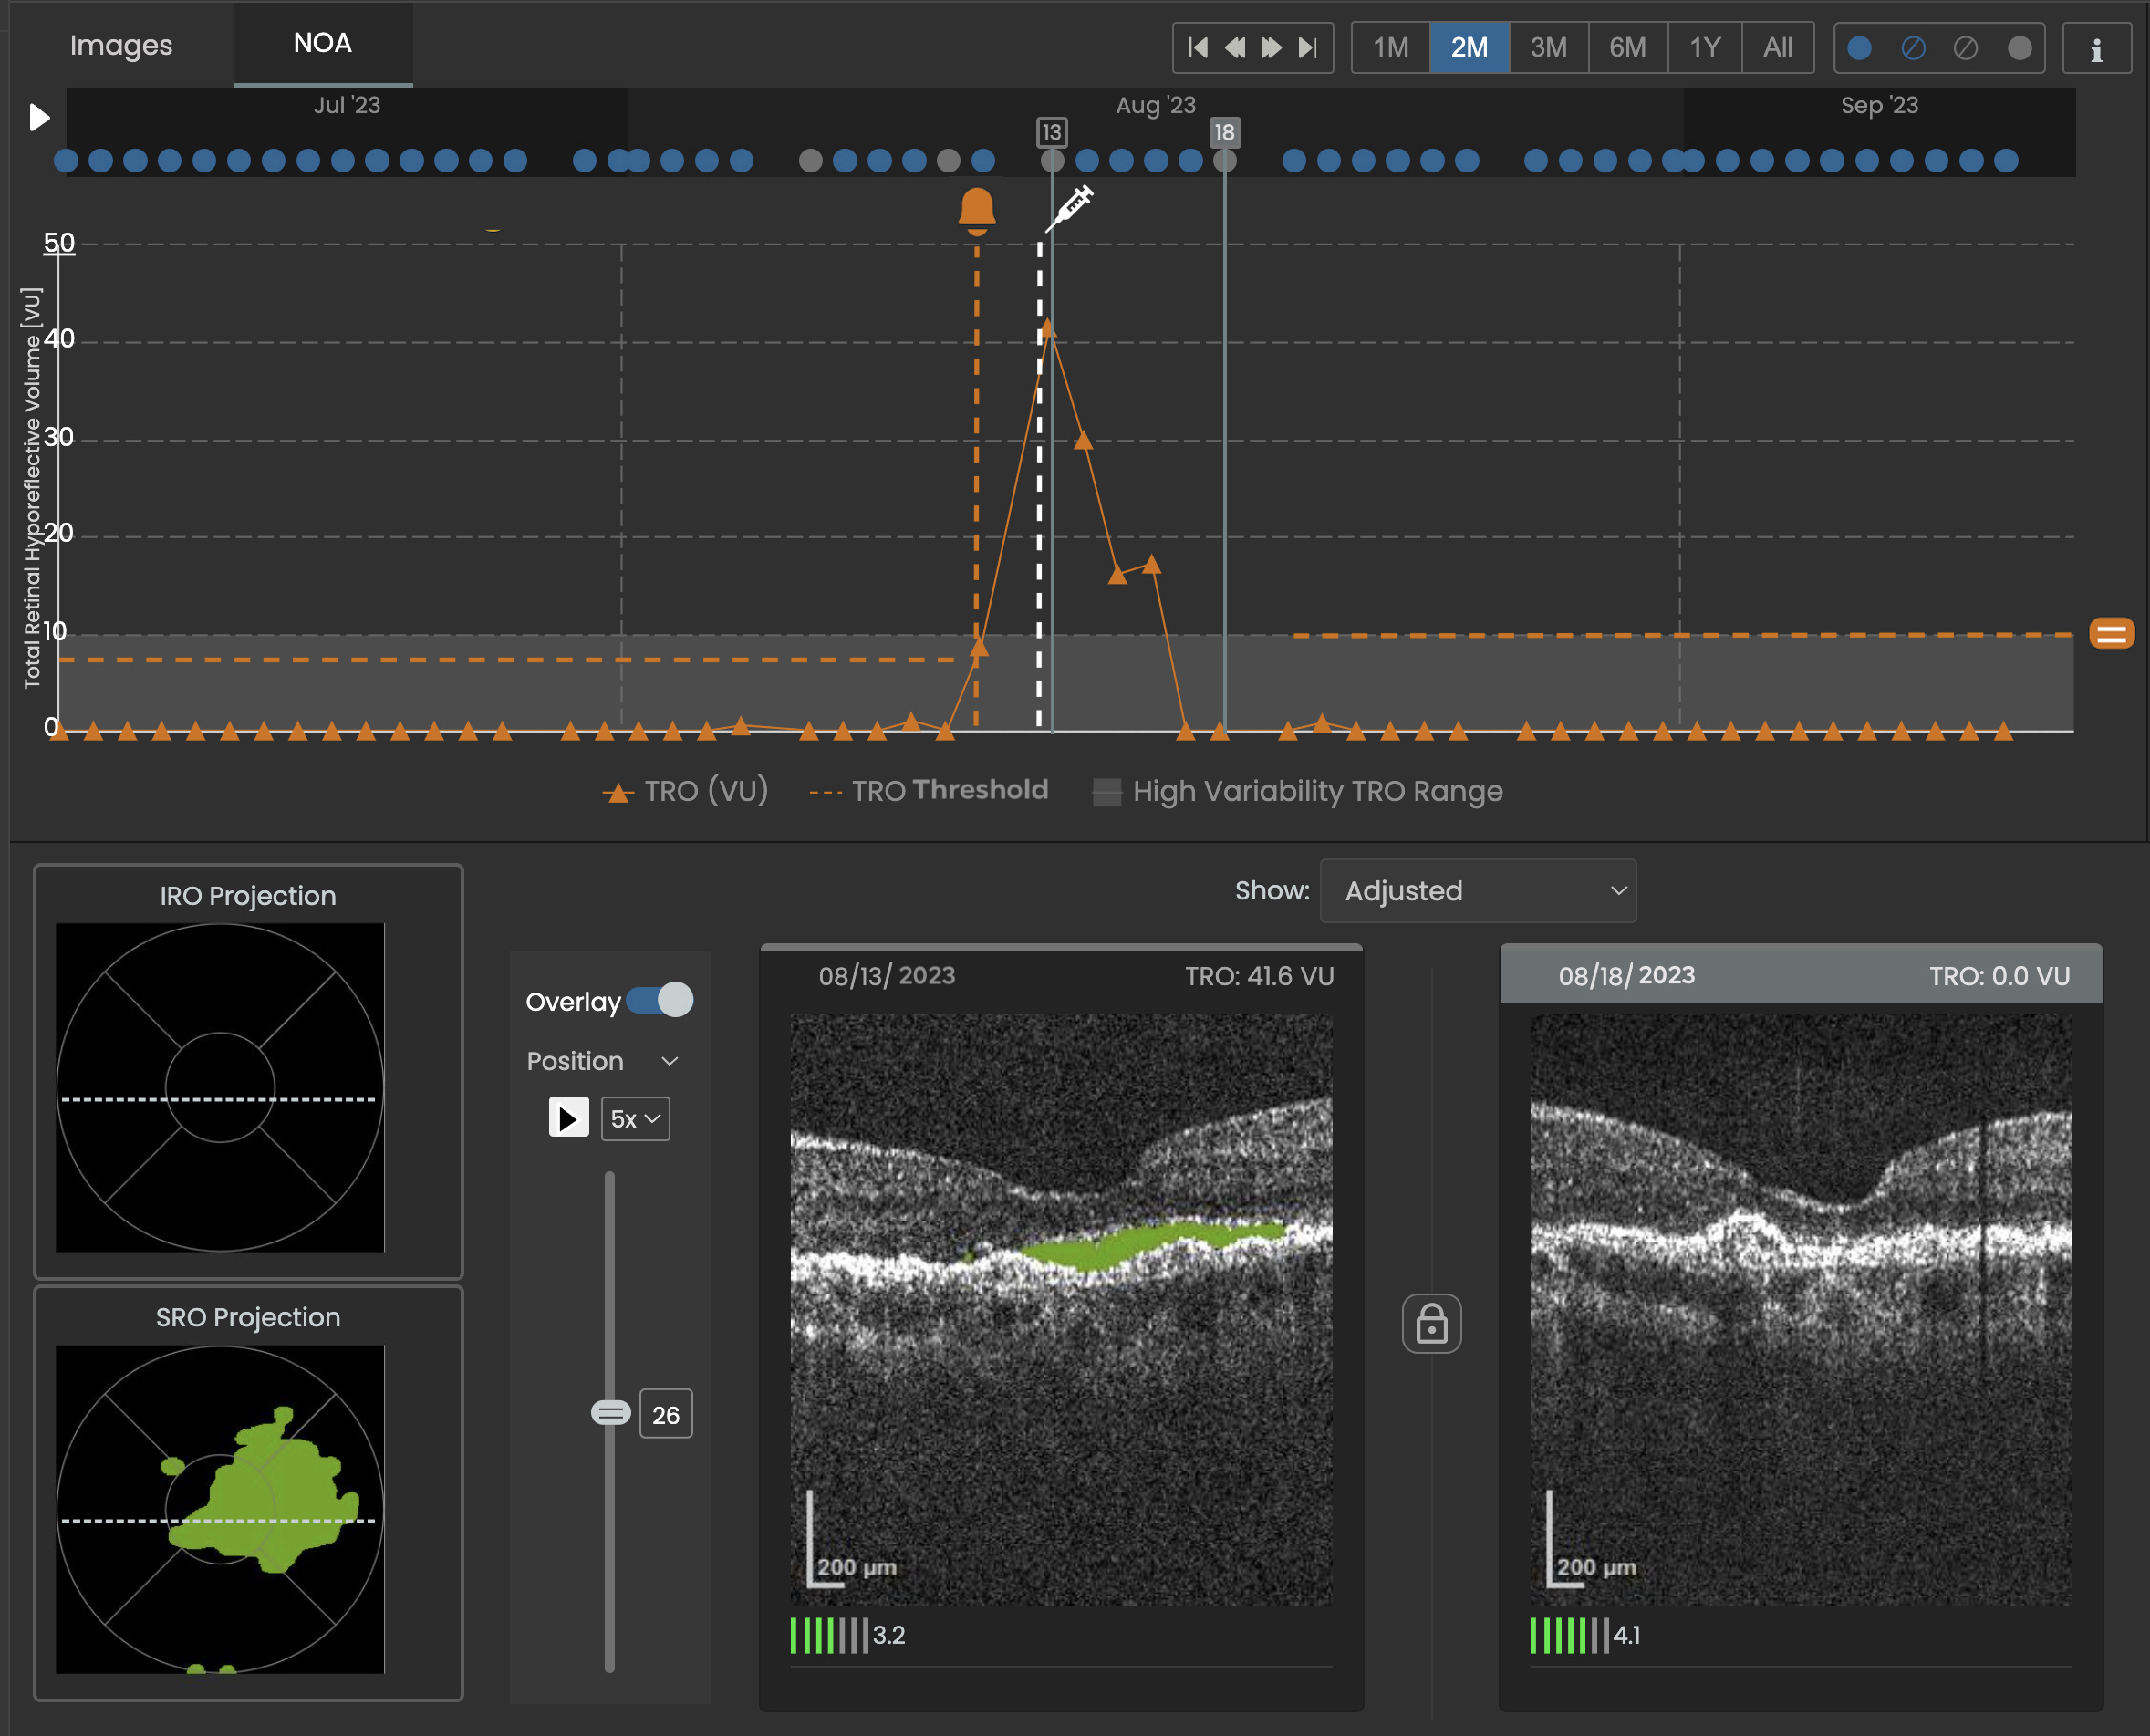

Figure 1: SCANLY Home OCT longitudinal disease biomarker volume trajectory with notification and treatment indicators (top) and corresponding projection map of subretinal hypo-reflective (SRO) spaces and B-scans (bottom).

Previous pivotal trials established that Notal's SCANLY Home OCT imaging is equivalent to in-office OCT for visualizing key AMD biomarkers.² Those studies also validated NOA’s accuracy in identifying hypo-reflective spaces, a key disease marker, in a cross-sectional setting.³ The latest research is the first to confirm NOA’s effectiveness in longitudinal tracking within a home-based environment.